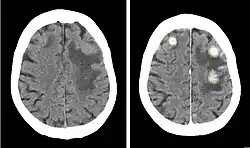

Computertomographie

Die Computertomographie spielt als schnell durchführbares und breit verfügbares Verfahren vor allem eine Rolle in der Notfallmedizin. Größere Metastasen grenzen sich als hypodense oder selten (Malignes Melanom, Chorionkarzinom) hyperdense Struktur gegen das normale Hirnparenchym ab. Da Metastasen aber auch isodens sein können, ist womöglich nur die raumfordernde Wirkung als Massenverschiebung oder die hypodense Formation des Perifokalödems abgrenzbar. Zentrale Einblutungen, wie sie insbesondere bei Metastasen von malignen Melanomen oder Nierenzellkarzinomen vorkommen, sind in der CT gut nachweisbar. In Abhängigkeit von der gewählten Schichtdicke liegt die Nachweisgrenze bei etwa einem Zentimeter, so dass kleinere Metastasen der nativen Computertomographie entgehen können.

Da die Computertomographie einen relativ geringen Weichteilkontrast aufweist, ist die Gabe von Kontrastmittel entscheidend: aufgrund der Störung der Blut-Hirn-Schranke im Bereich der Metastase kommt es zur Anreicherung von Kontrastmittel (Enhancement), das bei Vorliegen einer zentralen Nekrose häufig ring- oder girlandenförmig erscheint.